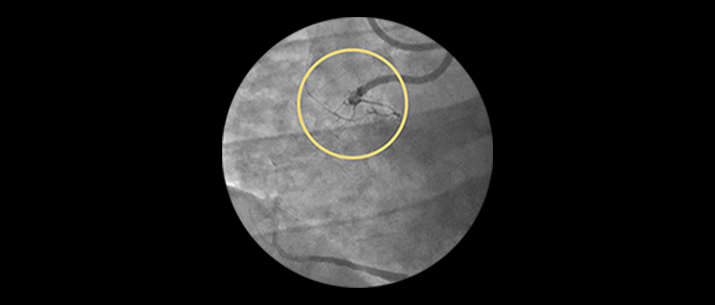

LAD In-Stent Restenosis: iFR and IVUS Co-registration, laser atherectomy, final DCB and stenting